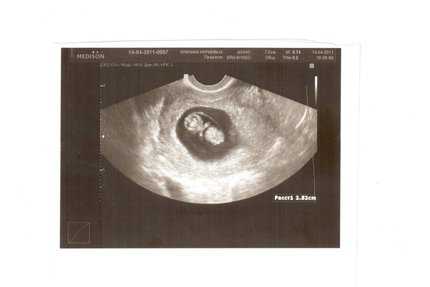

Вот основные события, которые сопровождают первые шесть акушерских недель. Менструальный цикл, предшествующий зачатию. Выход яйцеклетки или овуляция. Слияние яйцеклетки и сперматозоида в единое целое оплодотворение. Передвижение и имплантация яйцеклетки, которая преобразуется из зиготы в бластоцисту путем стремительного деления клеток. Изменение гормонального фона матери, благодаря чему можно точно подтвердить беременность при помощи аптечного теста. Формирование эмбриона. Из вышеприведенного списка становится понятным, что проводить. УЗИ на первой акушерской неделе абсолютно бессмысленно. Только на первой эмбриональной неделе и, соответственно, на третьей акушерской, при проведении. УЗдиагностики можно подтвердить или опровергнуть успешность зачатия. Но, конечно же, это исследование не покажет сердцебиение и вес плода. Также хочу подчеркнуть, что течение первой акушерской недели не сопровождается такими симптомами, как болезненность живота и молочных желез, тошнота, резкие изменения эмоционального состояния, общее ухудшение самочувствия и снижение работоспособности.